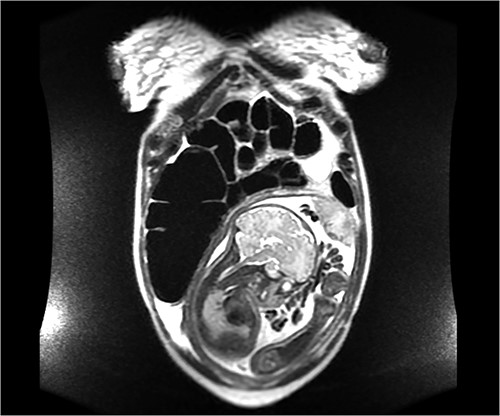

On hospital day 2, the patient became obstipated, and her abdominal exam had notable distension with persistent right upper quadrant tenderness. An abdominal magnetic resonance imaging (MRI) was performed revealing dilated small intestine with air-fluid levels and an inverted-appearing, prominent cecum (Figs. 1 and 2). The patient was diagnosed with an acute abdomen from probable cecal volvulus versus appendicitis and was urgently taken to the operating room for cesarean section (c-section) to facilitate abdominal exploration. After delivery of the child, a cecal bascule was found, with a severely distended cecum (Fig. 3). Because the cecum and ascending colon were deserosalized, a right hemicolectomy with primary ileocolic anastomosis was performed. The patient had return of bowel function on post operative day 5 and was discharged home on day 7.

Coronal image of the same MRI showing a dilated cecum displaced superiorly, consistent with a cecal bascule.